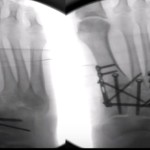

Surgical treatment of Calcaneal fractures

Courtesy: Saqib Rehman Associate Professor Director of Orthopaedic Trauma Temple University Philadelphia Pennsylvania USA www.orthoclips.com